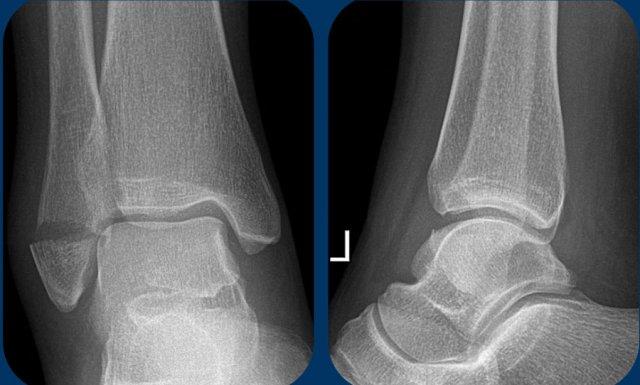

Giai đoạn 1

Đây là hình ảnh điển hình của gãy xương bứt rời hoặc gãy do lực kéo giật ở mắt cá ngoài.

Mảnh xương bứt rời khá lớn. Thông thường hơn, mảnh bứt rời có kích thước nhỏ.

Đây là gãy xương Weber A giai đoạn 1, có tính ổn định.